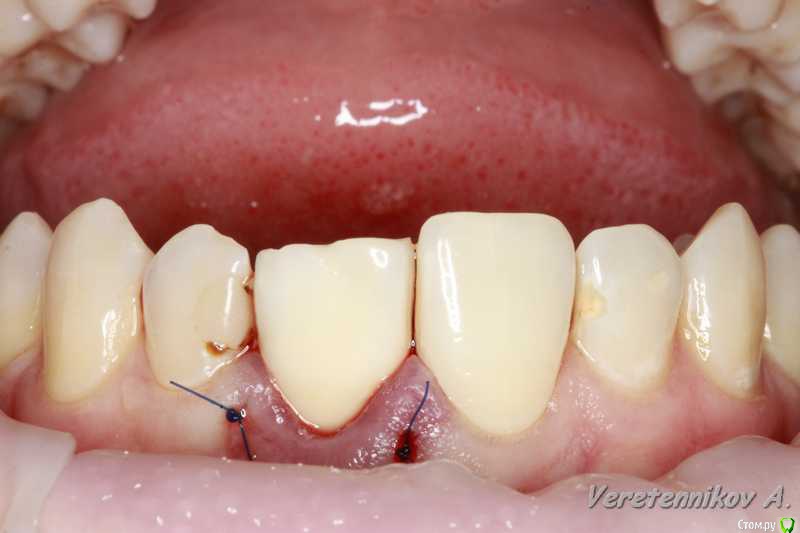

an_ver Опубликовано 15 декабря, 2015 Поделиться Опубликовано 15 декабря, 2015 Травма 21, немного сместился,удаление,имплантация SPI 4.2*13,ГенОсс+ ауто со сверла,для временной коронки использован свой зуб)),немного укоротили реж.край,чтоб не травмировать,унифлекс 5/0 18 Ссылка на комментарий